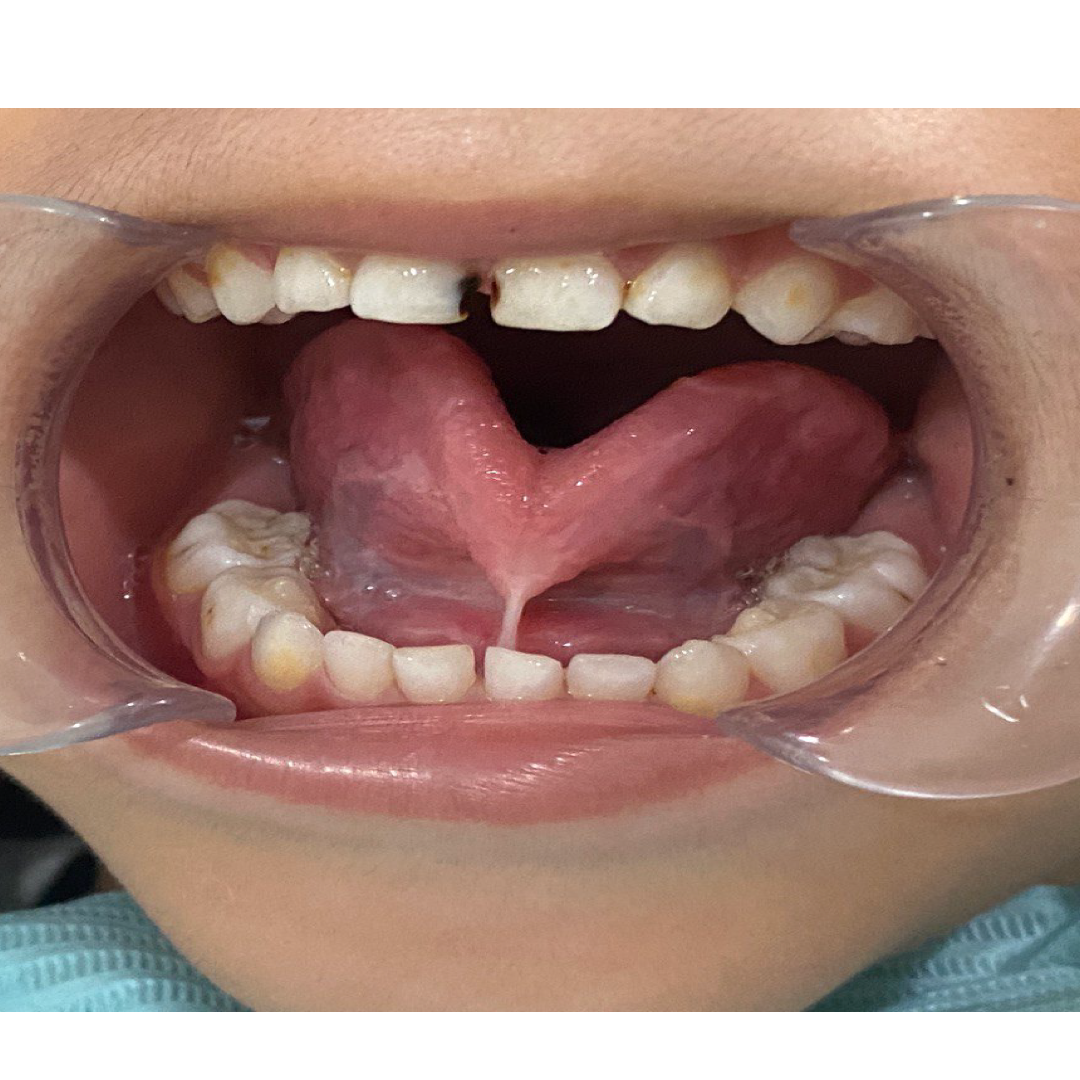

1. Tongue Tie (Ankyloglossia)

A tongue tie occurs when the tissue (lingual frenulum) under the tongue is too short or tight, restricting tongue movement.

📸 Before: Restricted tongue movement, speech/latch difficulty

📸 After: Freer tongue movement, improved function